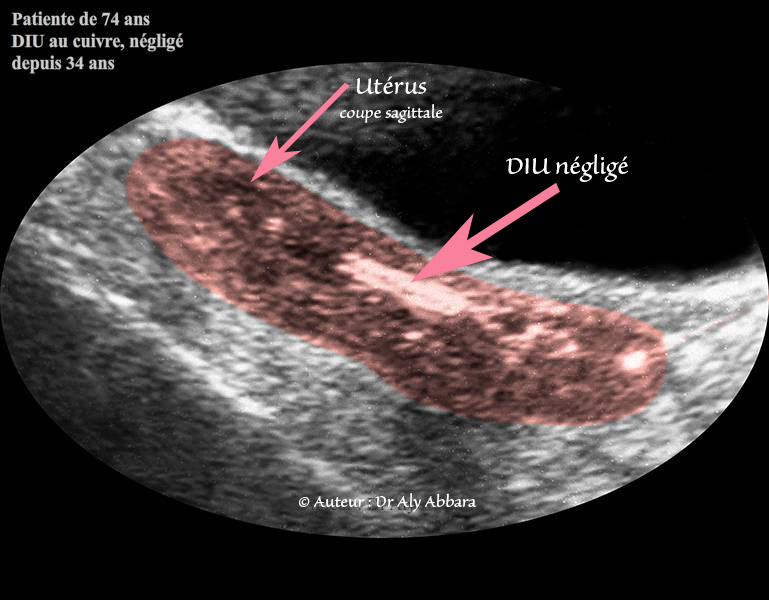

L'aspect échographique puis une image clinique montrant un dispositif intra-utérin (DIU - stérilet), au cuivre, négligé dans la cavité utérine durant 34 ans et découvert fortuitement à l'âge de 74 ans.

Sur l'image clinique on constate qu'il s'agit d'un stérilet au cuivre : le fil de cuivre semble oxydé, aminci, altéré, et partiellement fragmenté.